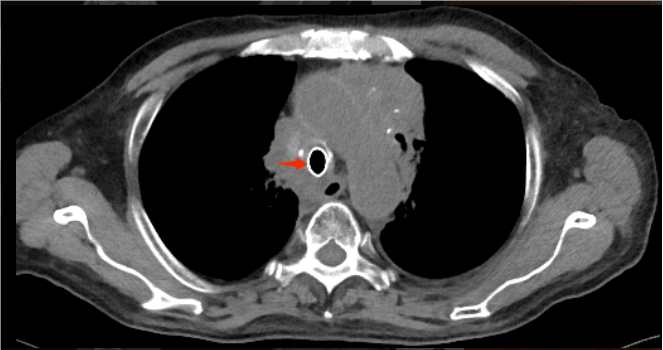

72岁的程爷爷,因“确诊肺癌5年余,咳嗽、咳痰伴间断咯血两个月”入院。检查发现其左肺鳞癌已进展至Ⅳ期,肿瘤侵犯导致气管中下段及隆突区域形成约4.5厘米的极重度狭窄,严重影响呼吸功能,同时患者合并心房颤动、心包积液等多系统并发症,治疗难度极高。

术前胸部CT见患者气道狭窄,呈一缝隙

术后复查胸部CT见气道通畅